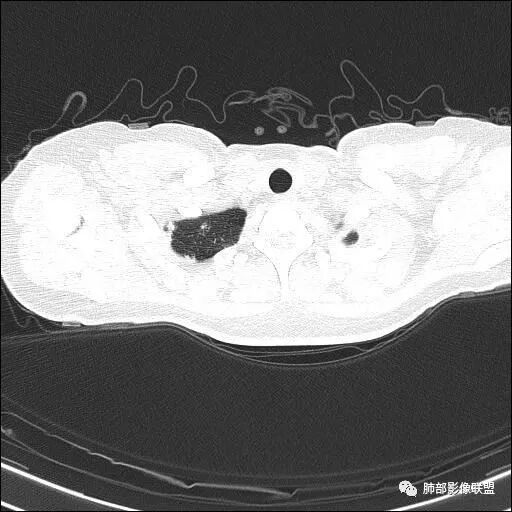

两肺多发病灶

分布特点:上肺胸膜下

图太少了,不连续,都是切面问一句:大家不觉得是沿间质分布的吗?网格状吗肿瘤不考虑吧如果单独拿这一个出来,要警惕肿瘤

全部拿出来,好像就不符合

局限,内部密度低

结核不支持,结核,如果空洞,内部干净,壁光滑这个不符合考虑肺气肿合并感染

觉得还是以网格为主,就是间质为主的特点